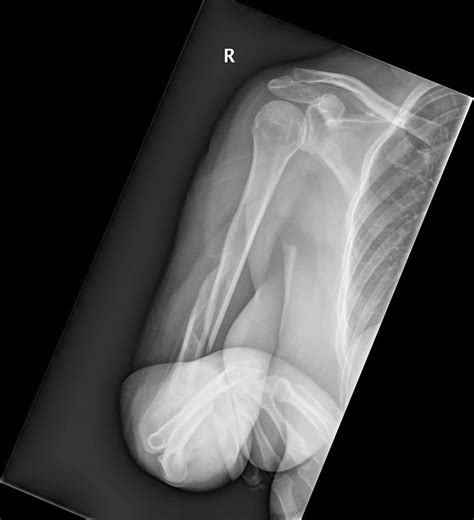

Diagnosing a Humerus Bone Break

Diagnosing a humerus bone break involves a combination of physical examination and imaging tests. The diagnostic process typically includes:

• Physical Examination: A healthcare provider will assess the arm for pain, swelling, and deformity.

• X-rays: Imaging tests such as X-rays are used to visualize the bone and determine the type and severity of the fracture.

• CT Scans or MRIs: In some cases, more detailed imaging like CT scans or MRIs may be required to assess the extent of the injury.

Types of Humerus Bone Breaks

Humerus bone breaks can be classified based on their location and pattern. Common types include: